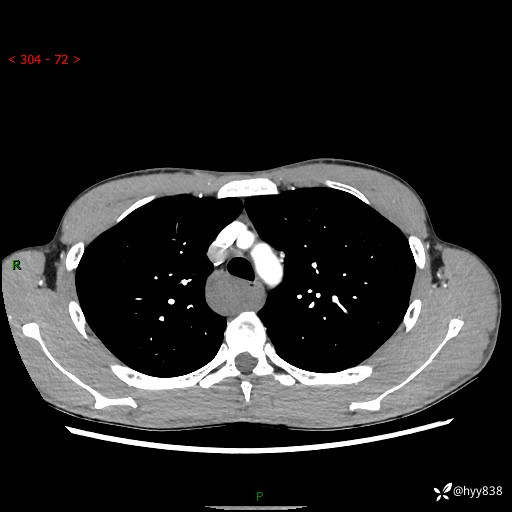

年轻男性,发现后纵隔占位1周余。征象简单,难在定位---结果公布~

现病史:患者于1周前体检行检查发现后纵隔占位,患者平素无明显咳嗽咳痰,无心慌、胸闷、胸痛、呼吸困难、低热、盗汗,无头痛、头晕,无腹痛、腹胀等不适。现患者欲求进一步治疗,遂来我院就诊,以“纵隔占位”收入我科。 患者自起病以来,精神可,睡眠可,饮食可,大小便正常,体重无明显改变。

胸部CT平扫+增强